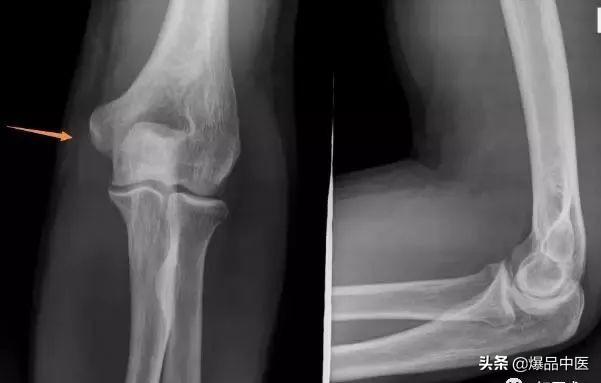

肱骨髁上骨折

1、肘关节后脱位:儿童肘关节后脱位极少见,脱位后肘后三角关系改变,患肢缩短,屈肘弹性固定;X线片可确诊。

2、肱骨外髁骨折:肿胀及压痛局限于肘外侧,有时可触及骨折块;X片摄片桡骨纵轴线不通过肱骨小头骨化中心。